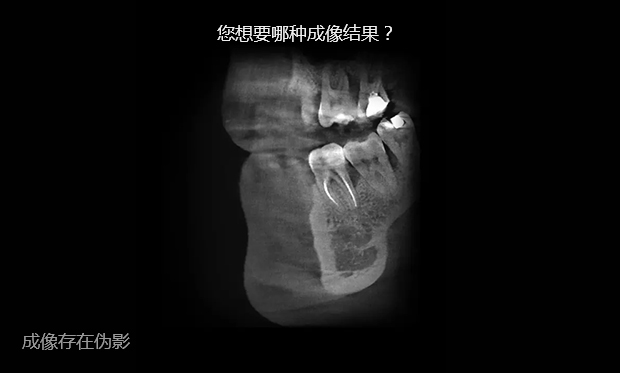

传统CT的二维扇形束扫描,投影数据是一维的,重建后的图像数据是二维的,经过重组的三维图像是连续多个二维切片堆积而成的,金属伪影较重。在数字化口腔诊疗的全链条中,数据精度决定治疗效果,对此,麦芽口腔采用三维锥形束X线取代扇形螺旋CT,二维的投影数据重建直接获取三维图像,牙齿或颌骨等硬组织结构成像质量更好。

清晰成像,辅助精确诊断

麦芽MAC数字化精确影像采集,广泛用于种植牙术前诊断设计、牙周疾病、牙体牙 髓病等科室的诊断,精确诊断能提升治疗精度。